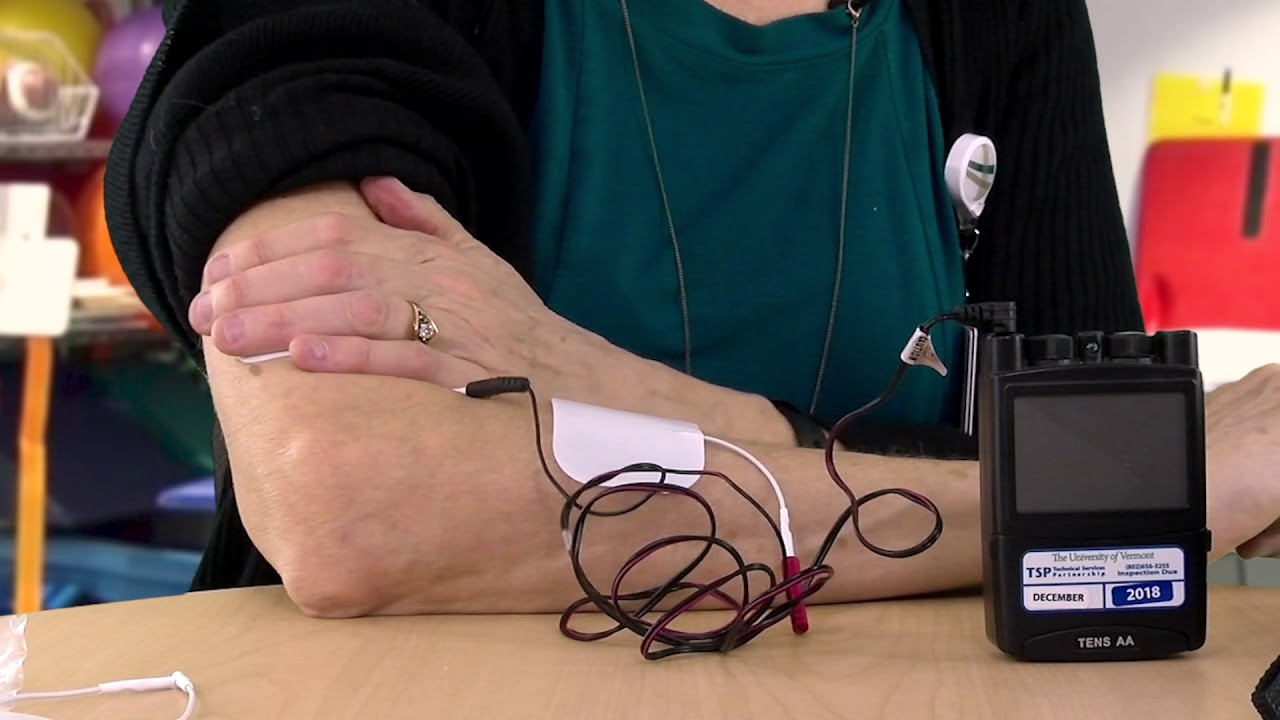

Read MoreTENS unit

A transcutaneous electrical nerve stimulation (TENS) unit is a battery-operated device that some people use to treat pain. TENS units work by delivering small electrical impulses through electrodes that have adhesive pads to attach them to a person’s skin.